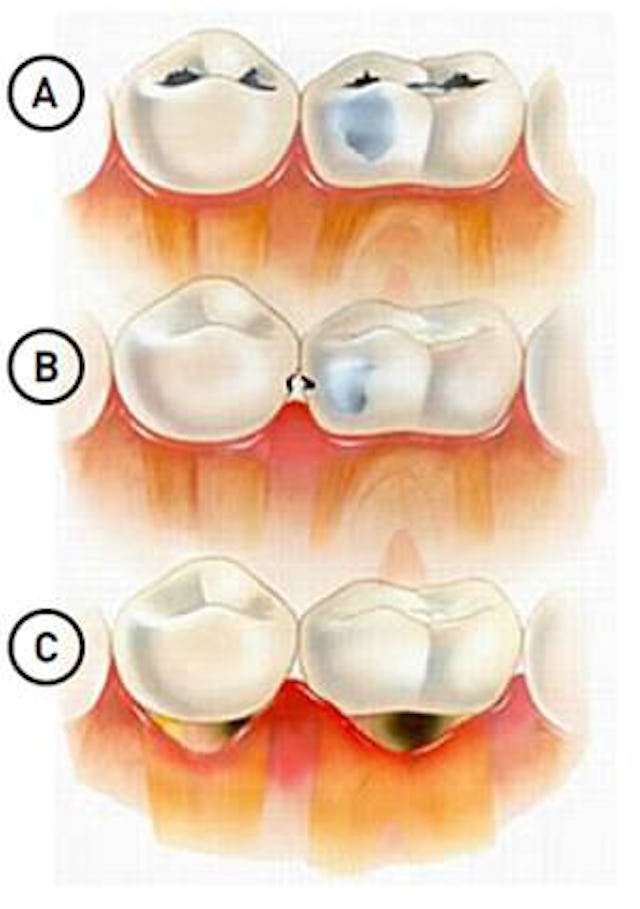

Bild A: Einfache, okklusale Karies (auf der Kaufläche)

Bild B: Approximale (oder interdentale) Karies, welche hier bereits durchschimmert. Diese Art von Karies ist allerdings meist nur auf dem Röntgenbild sichtbar. Ist diese einmal von der Seite sichtbar (sie schimmert durch), so hat sie in der Regel bereits eine beträchtliche Grösse erreicht, sodass eine Wurzelbehandlung nötig sein könnte.

Bild C: Zahnhalskaries (cervikale Karies)

Wie der Name es bereits sagt, entwickelt sich diese an den Zahnhälsen (Übergang von der Zahnkrone zur Zahnwurzel).